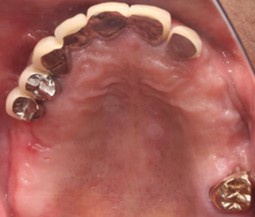

70代 男性

治療前

治療後

治療後- 年齢/性別

- 70代/男性

- 主訴

- 咀嚼障害

- 治療期間

- 1年7ヶ月

- 治療費

- インプラント¥440,000

骨造成¥300,000

サージカルステント¥200,000 - リスク・副作用

- 術後の腫脹 出血